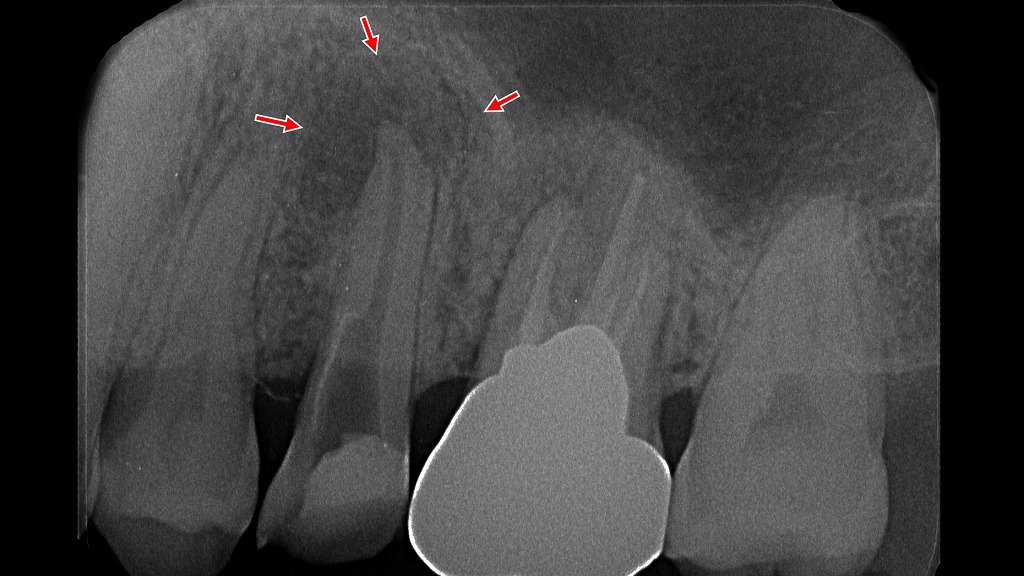

レントゲン画像から学ぶ

この写真は、根っこの先端に歯根嚢胞を形成したレントゲン画像です。矢印の部分にX線透過像(黒く映る部分)が認められ、ここに膿が溜まっています。

歯根嚢胞ができる原因は、根管治療がうまくいかず、歯根の中で細菌が繁殖するためです。歯根の形態が複雑になるほど、根管治療の難易度は上がります。

このように歯根嚢胞ができた場合には、再度根管治療をやり直す必要があります。それでもうまくいかない場合には、抜歯するか、外科的に歯根嚢胞を摘出する手術が必要になります。